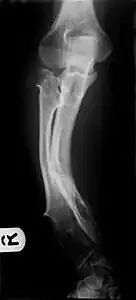

Multiple osteochondromas causing deformity of the forearm (shortening of the Radius with secondary bowing of the Ulna). -